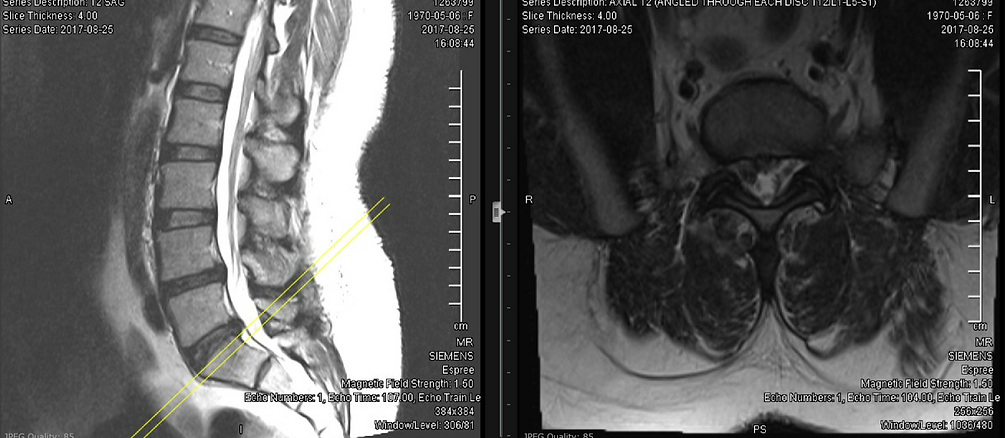

Transforaminal Epidural Steroid Injection